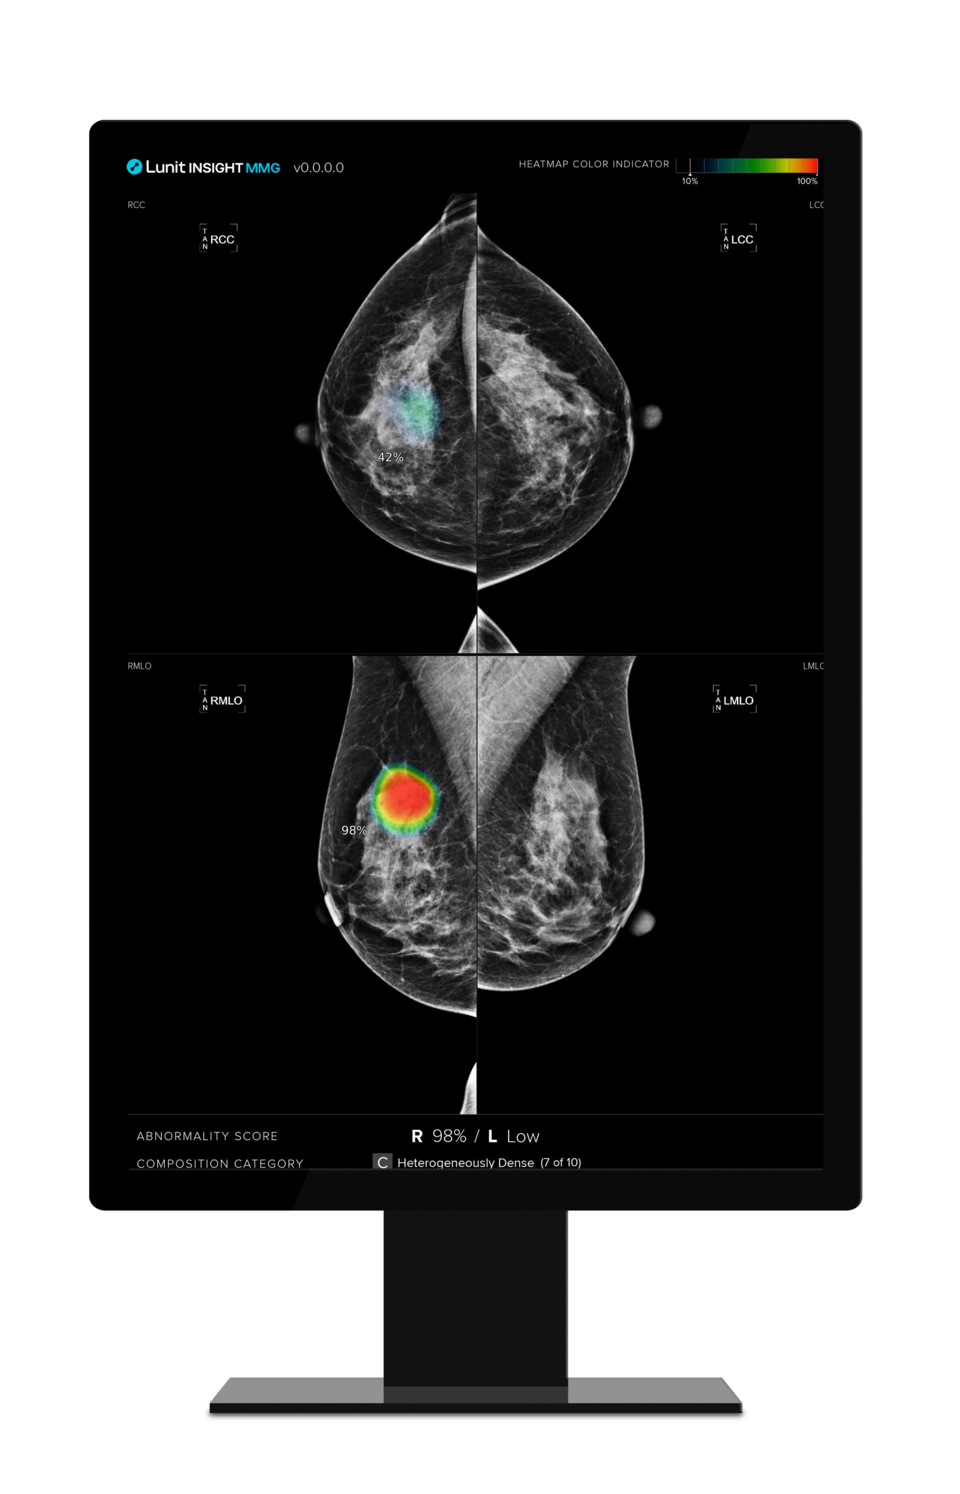

의료 인공지능(AI) 기업 루닛(대표 서범석)은 유방촬영술 AI 영상 분석 솔루션 '루닛 인사이트 MMG'의 유방암 진단 능력이 전문의 만큼 뛰어나다는 연구 결과가 국제학술지 '래디올로지(Radiology)'에 게재됐다고 13일 밝혔다.

연구팀은 2018년 5월부터 2021년 3월까지 영국 국가 유방 검진 프로그램(NHSBSP)에서 발생한 120건의 까다로운 진단 사례를 활용해 의료진 개인별 판독 결과와 루닛 AI 솔루션의 판독 결과를 비교했다. 그 결과, 루닛 인사이트 MMG는 전체 의료진과 유사한 수준의 유방암 검출 능력을 나타냈다.

의료진 552명이 실제 유방암 사례를 정확하게 진단한 민감도(Sensitivity)는 평균 90%였으며, 유방암이 아닌 사례를 정확하게 배제한 특이도(Specificity)는 평균 76%를 기록했다. 루닛 AI 솔루션의 민감도는 91%로 오히려 높았고, 특이도는 77%로 의료진의 판독 결과와 비슷했다.